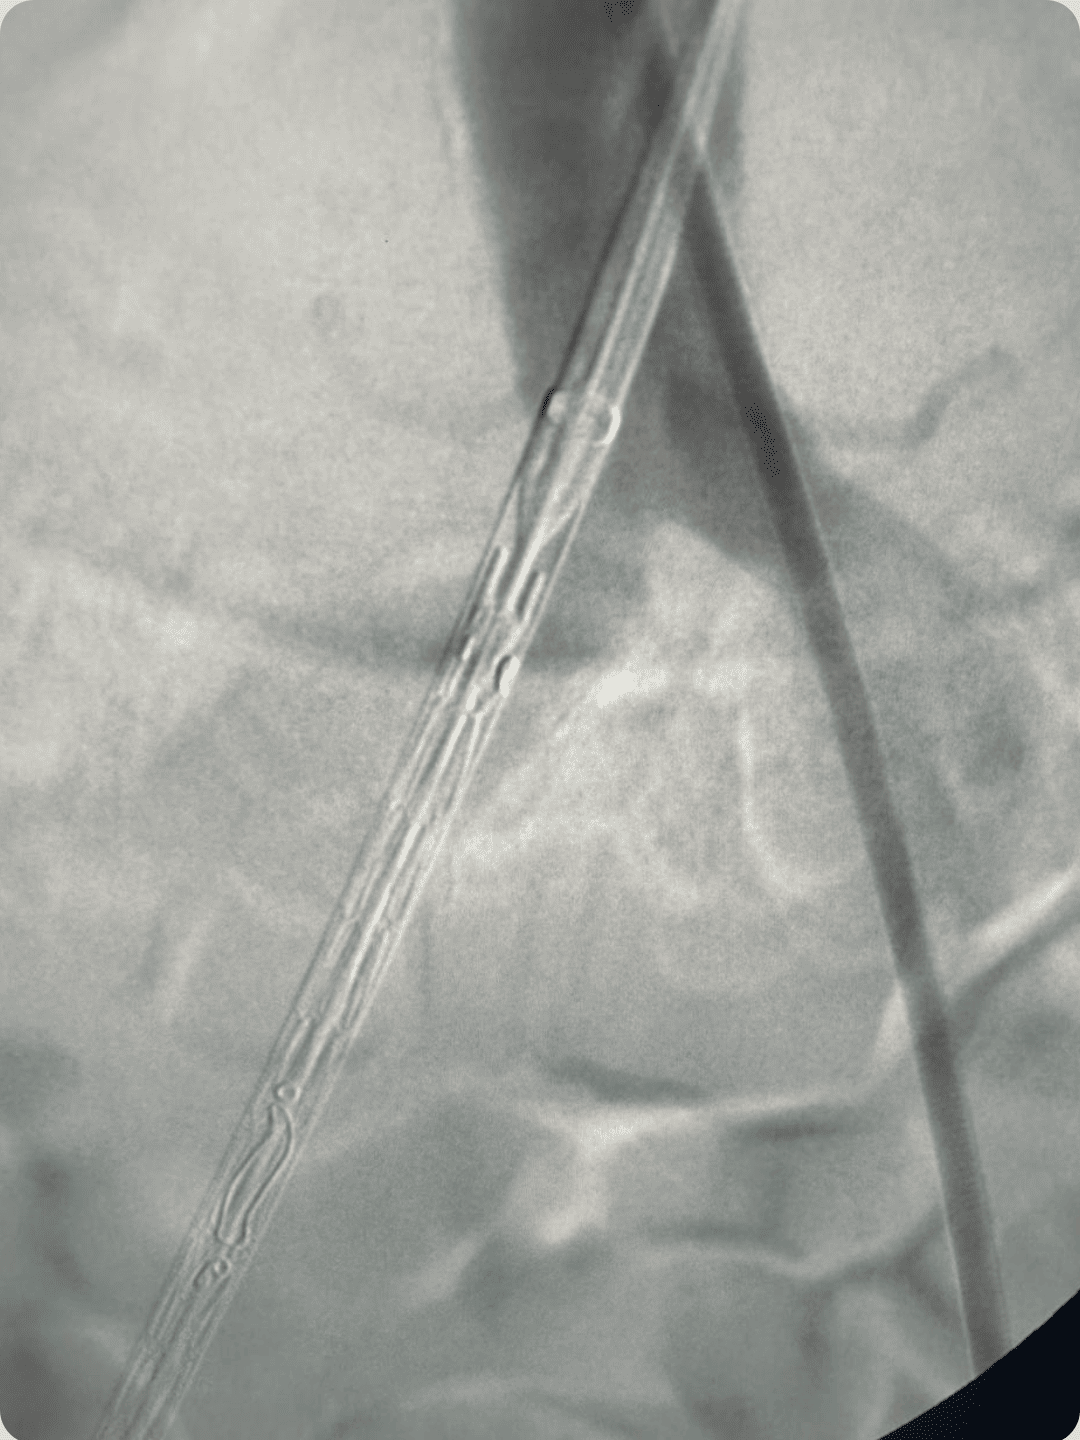

• Marcadores de visibilidade para posicionamento preciso

• Marcadores em formato de V nas extremidades proximal e distal do stent

• Boa flexibilidade e suporte estável

Mola especialmente projetada com fixação em espinha e trançado sobreposto